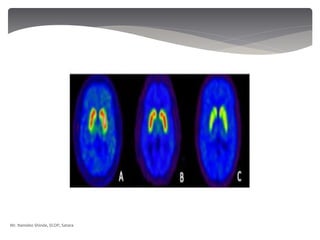

 IntelSite capsules are used for studying the drug

absorption.

 Radiotracers are tagged to the drug and absorption

and metabolism studied.